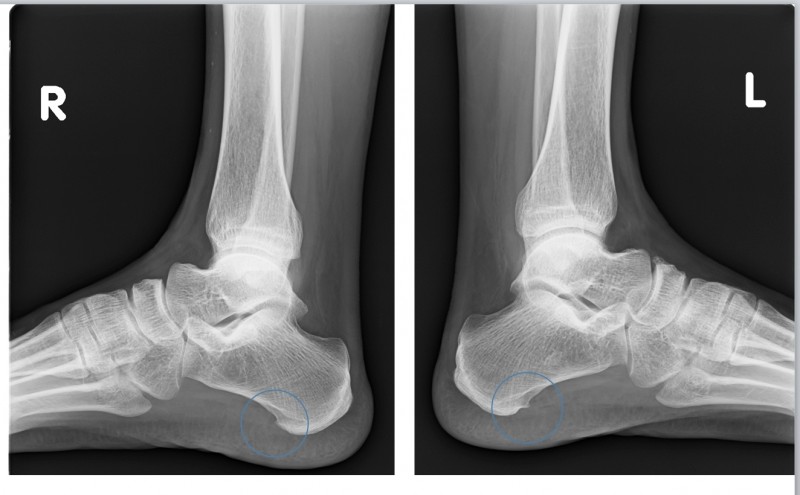

진단 방법: 육안으로도 확인 가능, X-ray로 변형 정도 측정

부산무지외반증 은 엄지발가락이 바깥쪽으로 휘어지면서 발 안쪽에 돌출부가 생기는 질환으로, 심한 경우 관절염으로 진행될 수 있으며 특히 여성에게 많이 발생합니다.

유전적 요인도 있지만, 좁고 앞이 뾰족한 신발을 오랫동안 신거나 발에 맞지 않는 신발 착용이 주요 원인입니다.

아침에 통증이 심해지는 이유는 수면 중 발의 자세가 변화하면서 변형된 관절에 압력이 가해지기 때문입니다.

또한 밤새 약간의 부종이 생긴 상태에서 아침에 갑자기 체중을 실으면 변형된 관절 부위에 통증이 더욱 심해집니다.